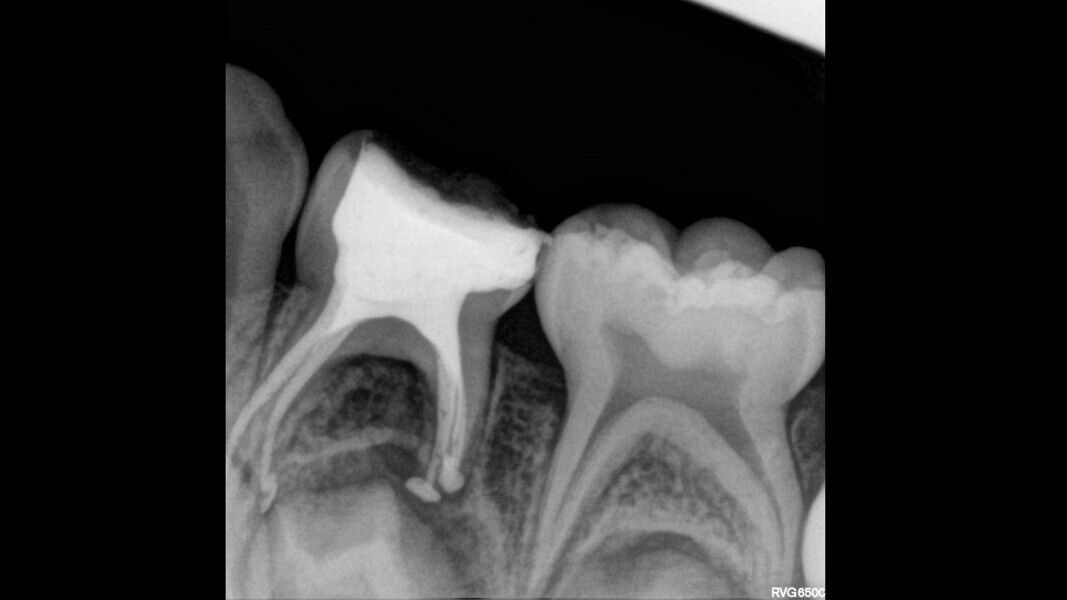

Case 1 (Figs. 1–4)

This female patient was 4 years and 7 months old and presented with pain that had lasted for several days affecting the mandibular right second primary molar. On clinical examination, a buccal gingival swelling and facial initial oedema were noted, and the tooth was found to have deep occlusal decay. Pulp necrosis and a symptomatic apical abscess were diagnosed. The patient was prescribed medication to control acute infection and rescheduled after the antibiotic treatment. At the second appointment, no pain was reported and the buccal abscess had partially receded. A decision was made to perform pulpectomy and restoration. Over-extrusion of the obturation material was observed. The 15-month re-evaluation confirmed no clinical or radiological signs of disease, and bone deposition was evident in the furcal area.